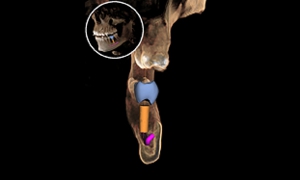

ドイツシロナ社はより安全なインプラント治療のためCMG(Cerec Meets Galileos セレックミーツガリレオス)という最新技術を生み出しました。CTは確かに優れていますが、今現在こまいかい所まではきれいに映りません。そこで、セレックによる3Dカメラのデータを取り込むことで、口の中とCTデータを融合させることにしました。そうすることで、最終補綴まで計算し、かつ骨の状態も把握できる最良の治療法が生まれたのです。

3Dカメラを使うセレックシステムとCTを3D解析できるガリレオスのデータを融合して、すべてコンピューターの中でインプラント埋入、アバットメントセット、かぶせのセットまでシミュレーションできてしまう、超先進技術です。まるで未来にきたように錯覚するかもしれません。これにより最終的な形が予測できる上、危険な治療ではないか、加えて必要な治療があるかどうかもわかります。